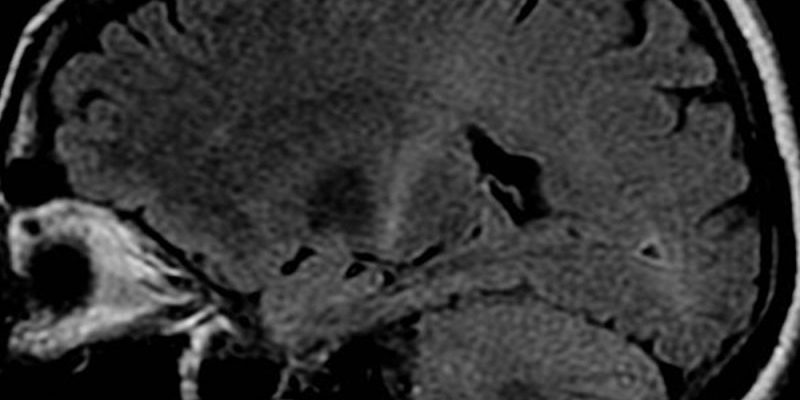

Ученые из Northwestern Medicine и Белградского университета определили электрофизиологический механизм, лежащий в основе заболеваний двигательного нейрона (ДН), что может стать ключом к созданию лечения от бокового амиотрофического склероза (БАС) и других нейродегенеративных заболеваний, таких как наследственная спастическая параплегия и первичный боковой склероз. Исследование, опубликованное в журнале Frontiers in Molecular Neuroscience, раскрывает молекулярные основы электрических сигналов от ионных каналов калия и натрия в клеточной мембране нейрона.

Данные показали, что на ранних стадиях заболевания ДН были неспособны поддерживать баланс возбуждения и торможения в кортикальной цепи, и их поведение было обусловлено динамическими изменениями в ключевых ионных каналах и их субъединицах.